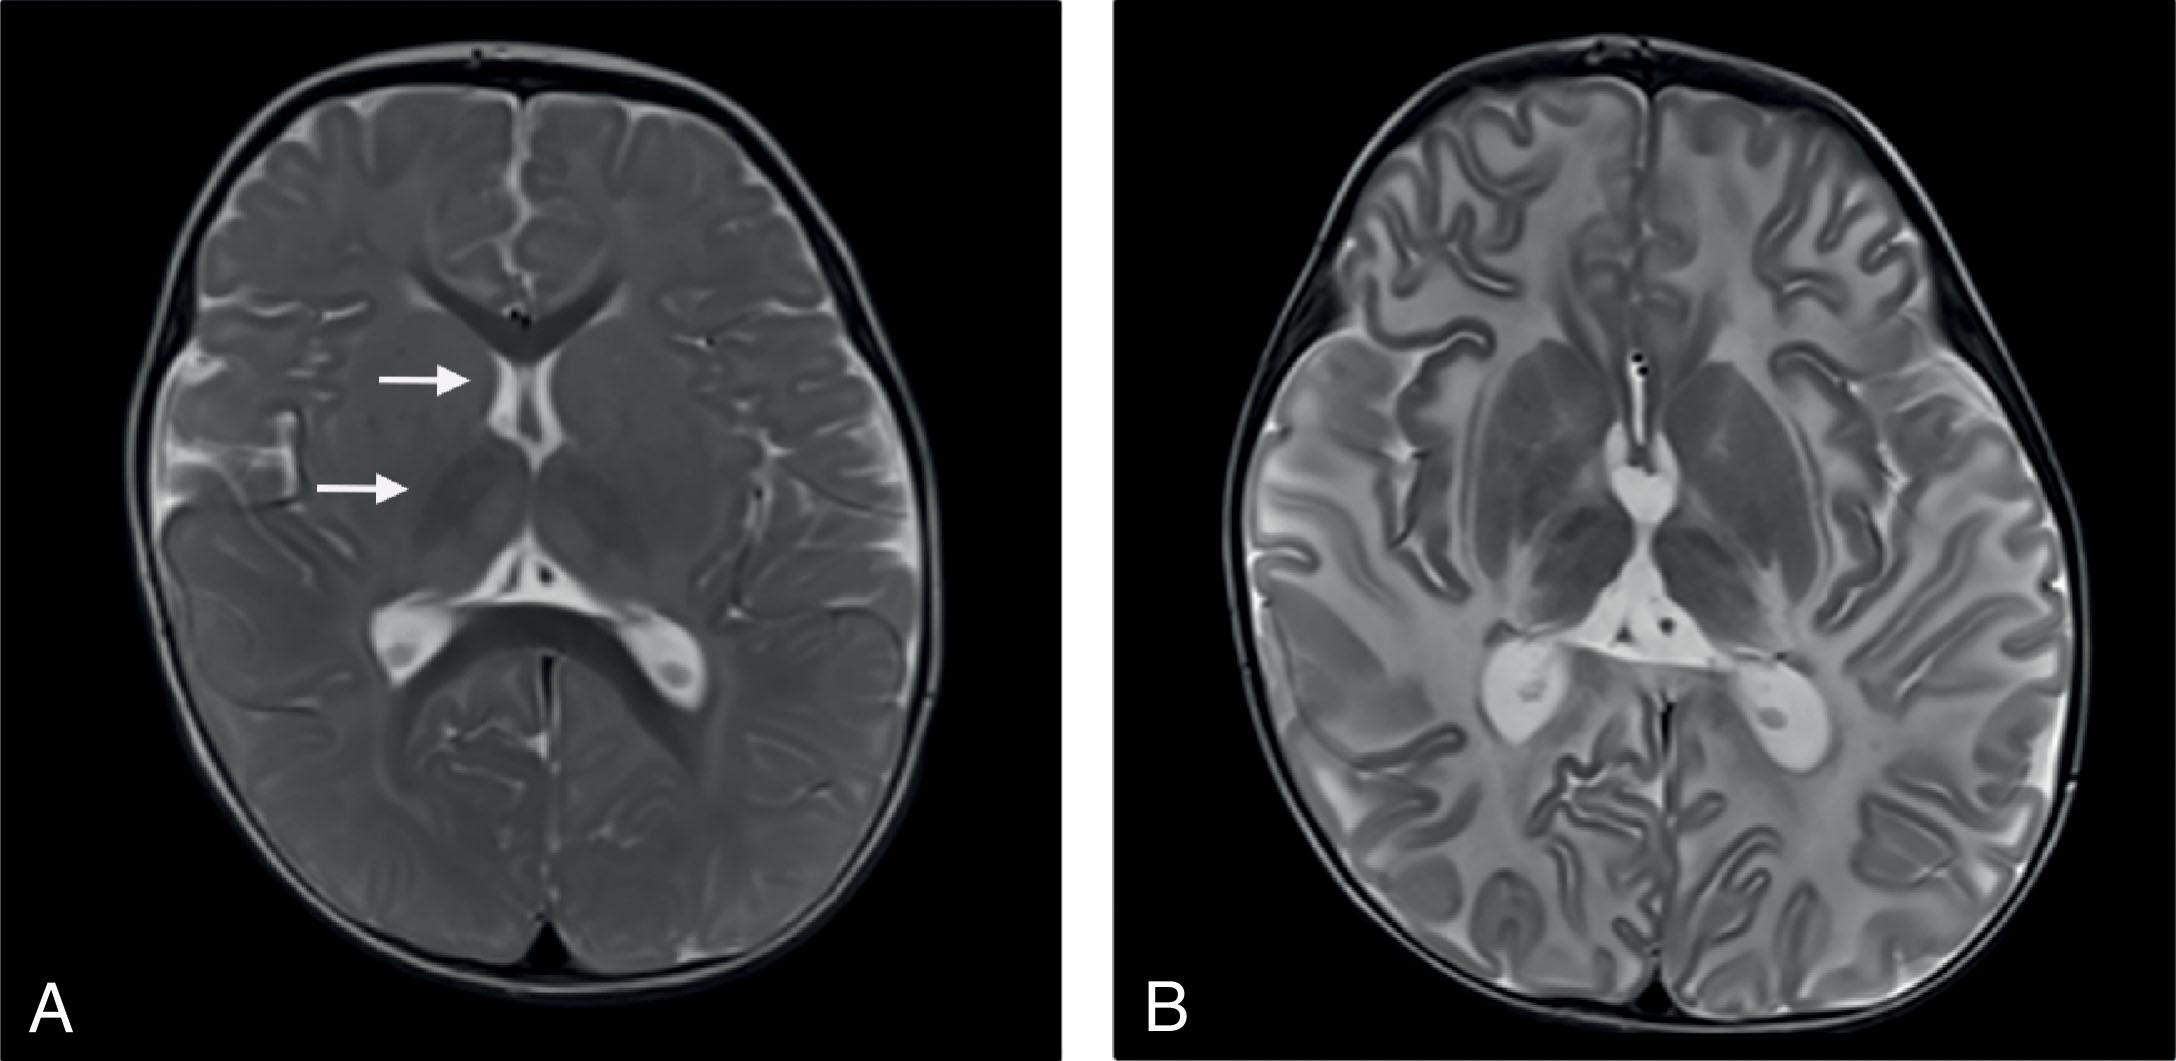

Fig. 33.2, Tay-Sachs disease: MRI. Axial T2-weighted images of an infant with developmental regression at 6 months of age found to harbor a pathogenic variant in the HEXA gene. (A) T2-weighed hypointensity is present in the thalamus bilaterally and head of the caudate (arrows) at 14 months of age, progressing to diffusely increased T2-weighted signal in the cerebral white matter by 28 months of age (B).